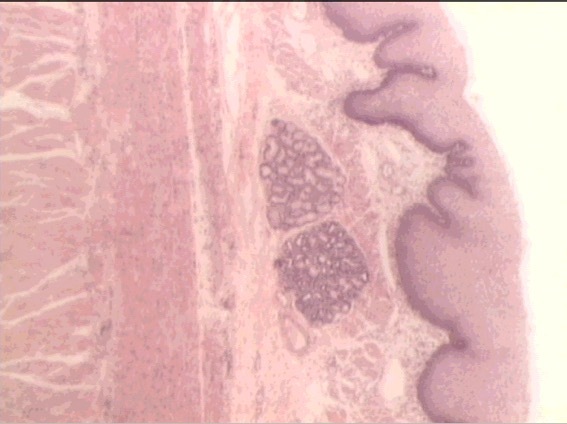

ileum

Peyer’s patch